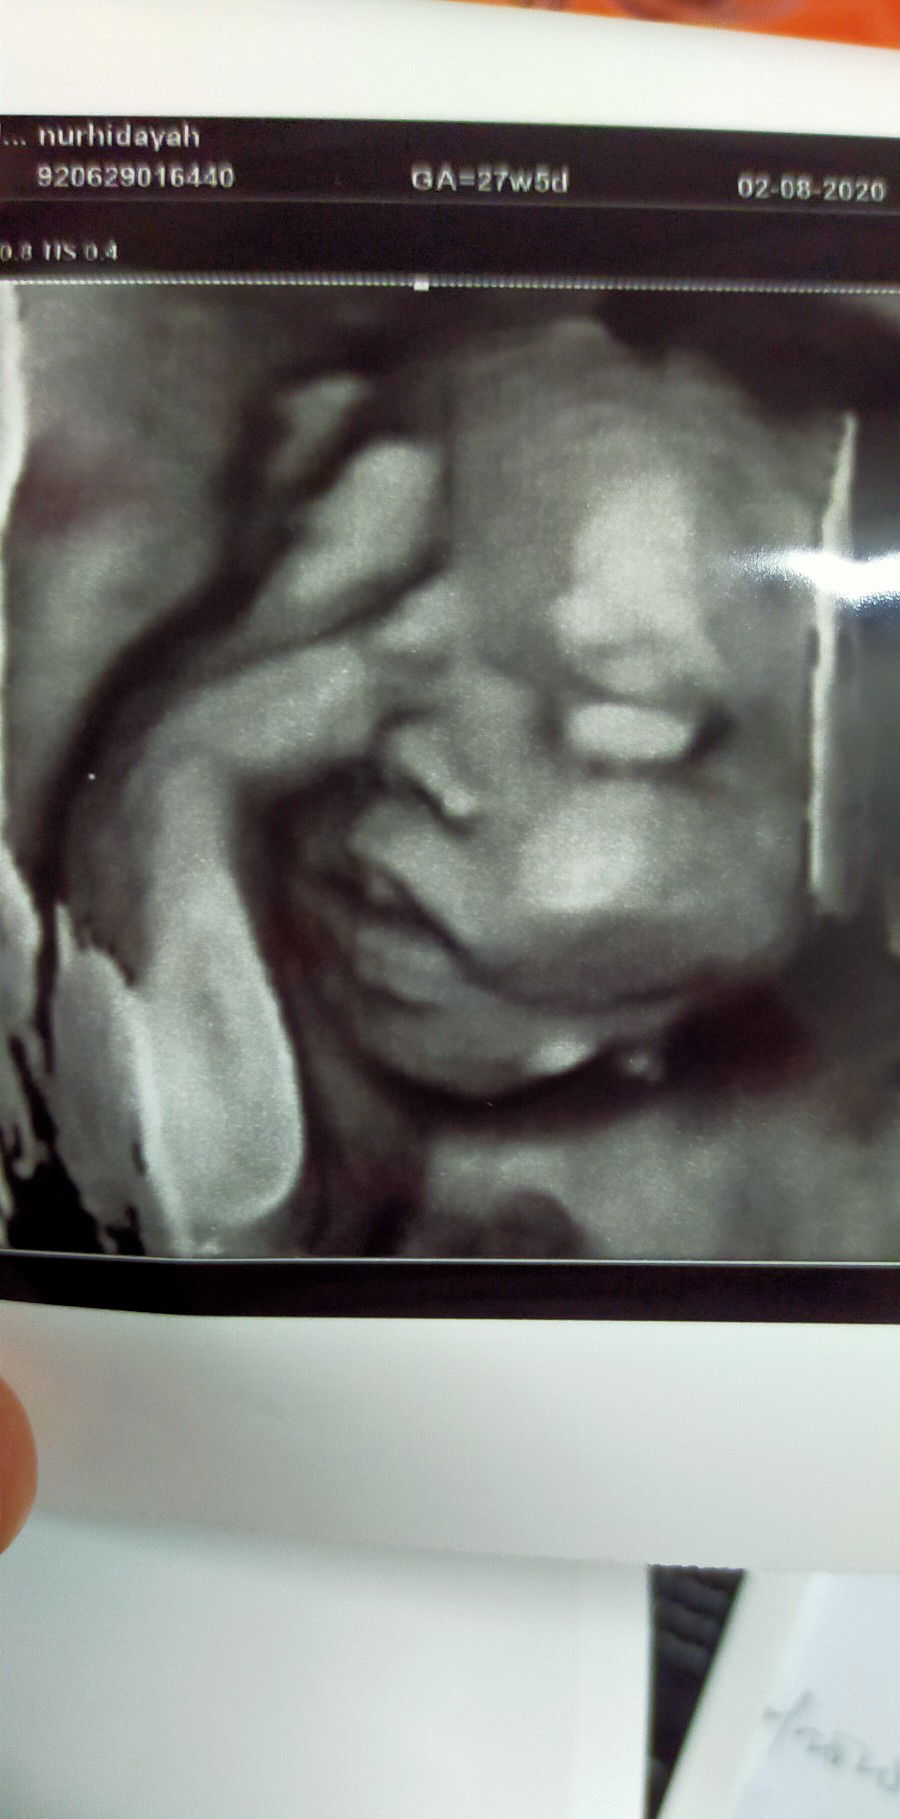

Scan muka baby 🥰🥰

Adik nyenyak tidur...tiba2 ibu dgn doktor kacau adik sbb nak tgk muka adik...apa la ibu ni (sambil tgn letak di dahi) 🤦🤦 #Hidung adik mancung dak 🤭 #Cuba teka adik boboy or gegirl #First pregnancy ..first journey💕